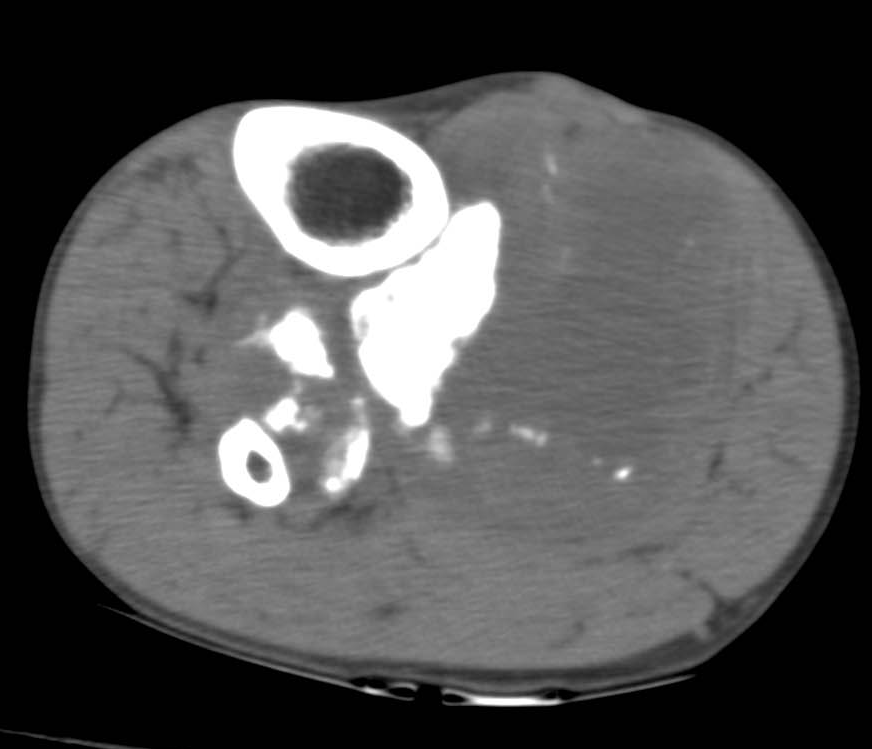

肿瘤内液 - 液平面

肿瘤内液-液平面多数是病灶内囊变出血所致,MRI T2W1 为上部呈高信号下部呈中低信号的液-液平面。CT 可为上部低密度下部高密度的液-液平面(图 32)。液-液平面常见于动脉瘤样骨囊肿、但也可见于骨内腱鞘囊肿(图 33)、囊性血管瘤病等其他肿瘤和肿瘤样病变。

图片

图 32.肿瘤内液-液平面:动脉瘤样骨囊肿

图 33.肿瘤内液-液平面:动脉瘤样骨囊肿